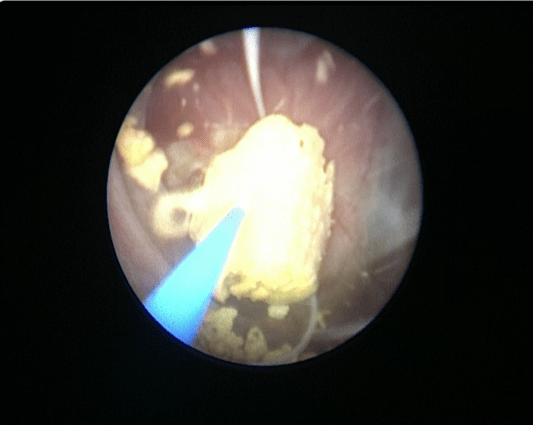

Пациенту выполнена трансуретральная эндоскопическая цистолитотрипсия, перкутанная нефролитолапаксия слева (рис. 6, рис. 7)

Пациент перемещен из литотомического положения в положение на спине. Под рентген контролем пунктирована нижняя чашка левой почки. Проводник проведен в лоханку и далее в верхнюю чашку. Установлен страховой проводник. Нефростомический ход поэтапно бужирован Выполнена нефроскопия, при которой определяется камень с желтоватой поверхностью в нижней чашке и лоханке левой почки, размерами 32х34 мм. Камень поэтапно фрагментирован с помощью лазерного литотриптера, фрагменты камня, детрит и внутренний мочеточниковый стент удалены эндоскопическими щипцами через нефростомический ход. Рентген контроль, в ЧЛС левой почки установлена нефростома.